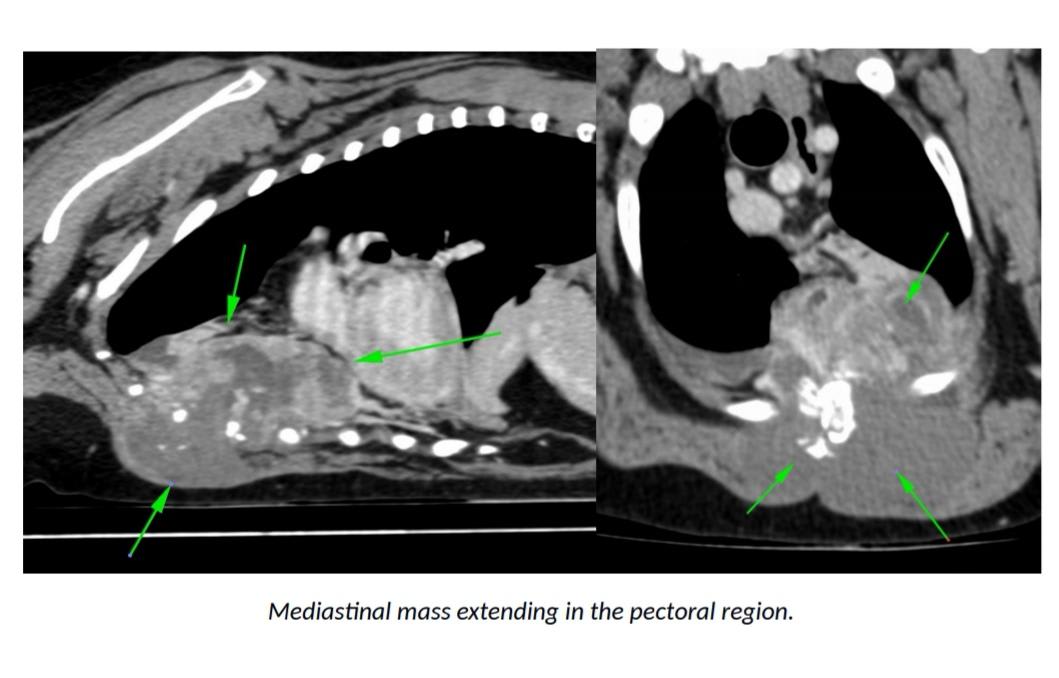

Thanks for using Petco Pet Education Center, formerly Petcoach! The fact that these biopsies have come back inconclusive does not mean that this is not cancer. Unfortunately, this is very likely an aggressive form of cancer. After seeing these images, my main concern is that this is possibly a tumor arising from one of the ribs or sternebrae such as osteosarcoma for instance. In one of the images I see that there is likely pulmonary nodules which are most likely due to metastasis or spread of this cancer. It is hard for me to advice further without being able to look at more images or know more about the case. I would encourage you to check in again with them as another biopsy could be performed. Also, if there is truly already signs of metastasis, the treatment options and prognosis are also limited. I would mention to them the possibility of being referred to a veterinary oncologist who can look at the case with more details and advice further. I really hope they can help you and your boy!